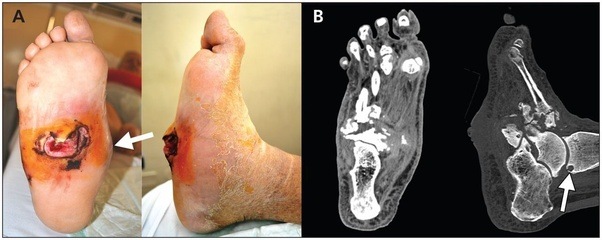

Foot Drop, Peroneal Nerve Injury - Neurologic Disease from www.videomd.com

For example if the cause is gout, patient may need anti inflammatory analgesics and pain killers to relieve pain. Foot Drop, Peroneal Nerve Injury - Neurologic Disease